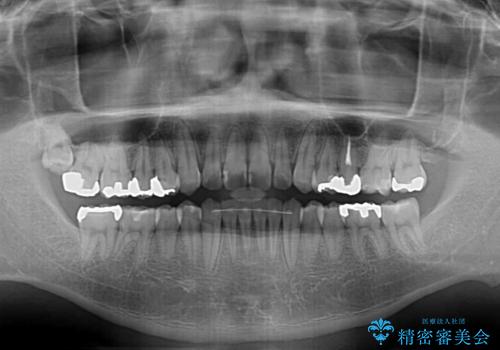

- 前歯のデコボコとクロスバイトを気にして来院された患者様です。

前歯を早く整えたいとの希望があったので、ワイヤー矯正にて短期間でクロスバイトを解消し、その後インビザラインにて整えることとしました。

インビザラインによる前歯のクロスバイト改善におけるリスクとして、前歯歯髄充血・歯髄壊死が挙げられます。

ワイヤー矯正を併用する目的として、短期間でデコボコやクロスバイトを改善する他に、歯髄充血リスクを低減させるというものがあります。